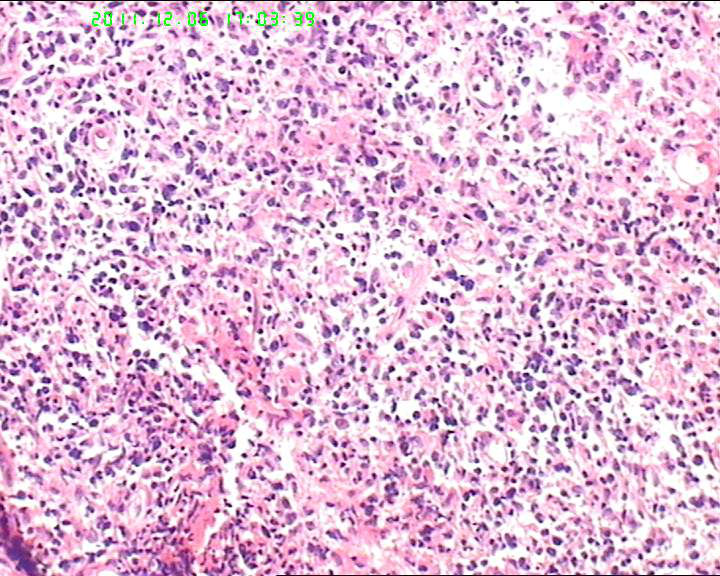

53岁女性患者,鼻腔肿物,中线恶网?韦格尔肉芽肿?

患者流脓涕1年,加重1月。左鼻腔息肉样增生物,质软,易出血。

送检灰白色绿豆大组织4块。

组织内见大量形态各异的异型明显的细胞,弥漫分布,背景见肿瘤素质,首先考虑结外NK/T细胞淋巴瘤,鼻型;恶黑待排。

恶性淋巴瘤(NK/T)

横纹肌肉瘤,恶黑,血管肉瘤,NK/T等